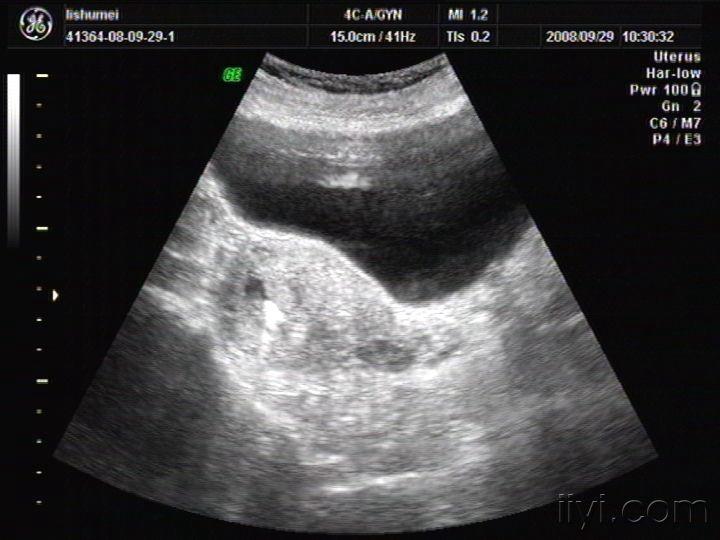

异位妊娠的超声诊断

超声检查诊断宫外孕的比较研究 经腹超声检查附件包块,胚芽,假孕囊,心